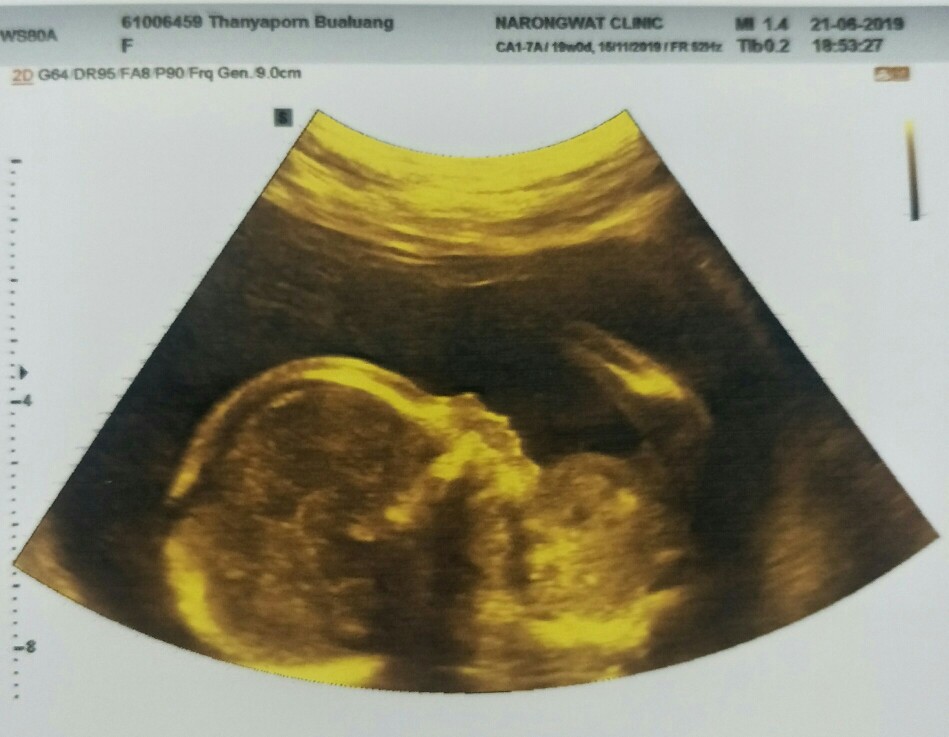

จมูกลูก

มีบ้านไหนซาวด์แล้วจมูกโด่งแบบนี้มั้ยคะ ออกมาจมูกน้องโด่งแบบนี้รึเปล่า? นี่คุณหมอบอกโด่งมาก?

ตอนซาวโด่งค่า คลอดประมาณ 7 พย. จะมาบอกอีกทีนะคะ 😍😍

บ้านนี่ซาวด์4มิติจมูกโด่ง ออกมาก็โด่งจ้า

ออกมาดั้งโด่งมากค่ะตอนซาวด์ไม่เห็นดั้งเลยค่ะ

แบบนี้โด่งมั๊ยค่ะ บ้านนี้จะคลอด7 พ.ค นี้จ้า😊😊